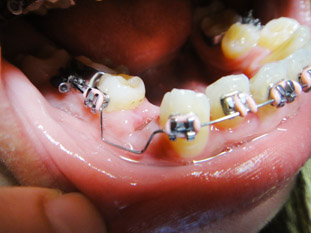

對於右下幾乎沒長出來的智齒念茲在茲,今天終於去拔掉它了!!

和左下同樣是水平長得又相當巨大,但差別是右下智齒幾乎沒有冒出頭(似乎根本看不到頭),

雖然矯正醫師沒有主動要求我拔除但因為實在腫太多次,且大臼齒附近總是有臭味(即使已經刷了牙),於是徵求矯正醫師同意後鐵了心趁現在還身體力壯復元正好的時候趕快一了百了! 矯正醫師非常贊成拔除它,因為能再生出一起空間讓牙齒後退。

這次是去矯正醫師介紹的「聖明牙醫」蘇醫師,在高雄捷運市議會站附近。我的4顆小臼齒都是去那拔的,感想:又快又準。

診所和醫師不同,當然和4年前拔左下的經驗不同。(之前的左下智齒是在附近的

新田牙醫拔的,也是醫術高明的醫生)